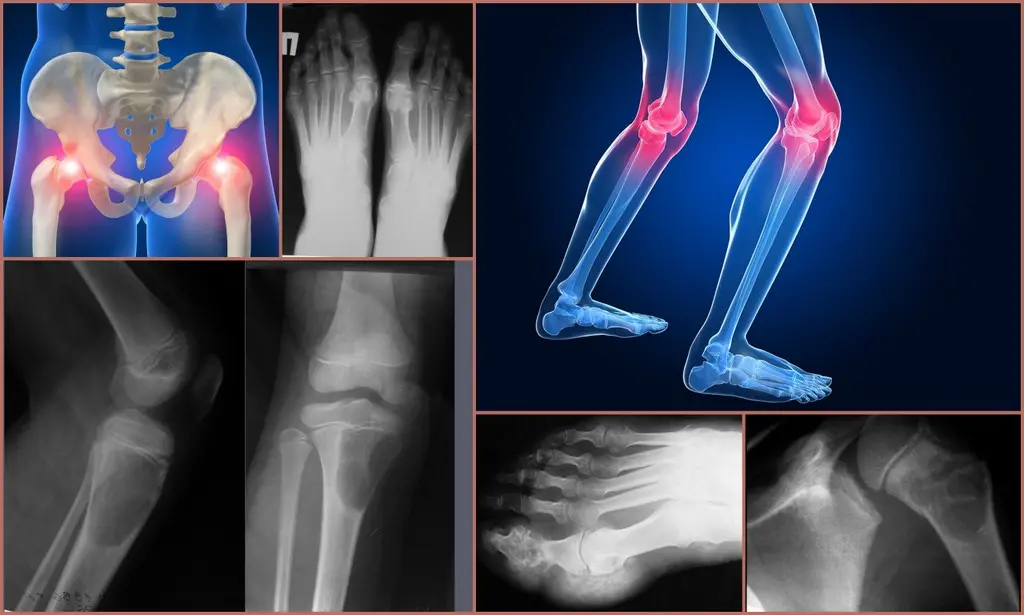

Для діагностики патології проводять такі аналізи та процедури:

- Загальне дослідження крові та сечі. При захворюванні характерна наявність ознак запалення, іноді анемії.

- Біохімічне дослідження крові. Оцінюють присутність C-реактивного білка, а також білкові фракції та загальний показник білка.

- Імунологічні аналізи. Виявляють наявність інфекції, виключають ревматоїдний артрит.

- Дослідження крові шляхом ПЛР. Це свідчить про генетичну природу розвитку патології.

- Бактеріальні посіви. Їх проводять для виявлення інфекції та уточнення різновиду патогенів.

- Аналіз синовіальної рідини. Він дає змогу виключити гнійний артрит.

- Рентгенографію. Її проводять з метою оцінки стану суглобів.

- Ультразвукове дослідження. Воно демонструє зміни у м’яких навколосуглобових тканинах.

- Артроскопію. Вона застосовується рідко, тому що відноситься до малоінвазивних методів. У процесі фахівець оцінює стан внутрішніх суглобових структур та може видалити патологічні утворення.